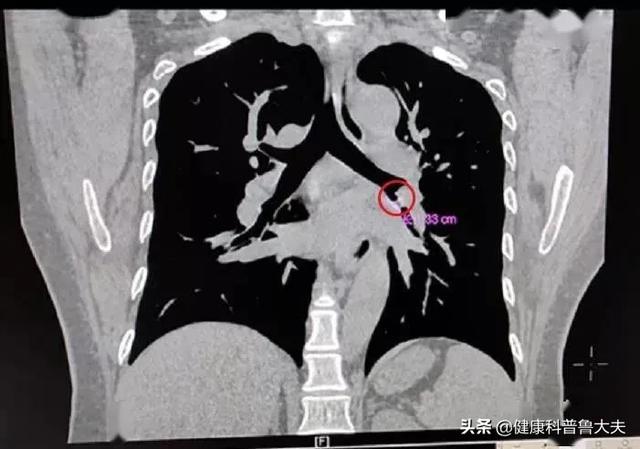

関連補助検査

これには、(1)肺CT、(2)肺機能検査、(3)誘発喀痰細胞診、(4)FeNO値、(5)アレルゲン皮膚検査および血清IgE、(6)24時間食道pH-マルチチャンネルインピーダンス値モニタリング、(7)気管支鏡検査、(8)咳感受性検査、(9)その他(末梢血Eos)が含まれる。

まず、咳の原因を調べる必要があります。例えば、上気道感染症、気管支炎、肺炎など、咳や痰が出やすい場合は、病院で定期的に血液検査を行い、CRP、カルシトニノーゲンなどを調べ、同時に肺のCTを撮ります。ウイルス感染によるものであれば、抗ウイルス薬を同時に使用することもできますが、医師の指導のもとで使用する必要があります。咳がより深刻な場合は、ネブライザー吸入療法を行うこともできます。ネブライザー吸入は皮膚や粘膜に直接吸収され、咽頭炎による炎症、乾いた咳に効果があり、非常に優れています。もし痰が多ければ,またいくつかの経口アミノブロミン内服液の治療効果を服用することができて,すぐに咳を和らげることができます。